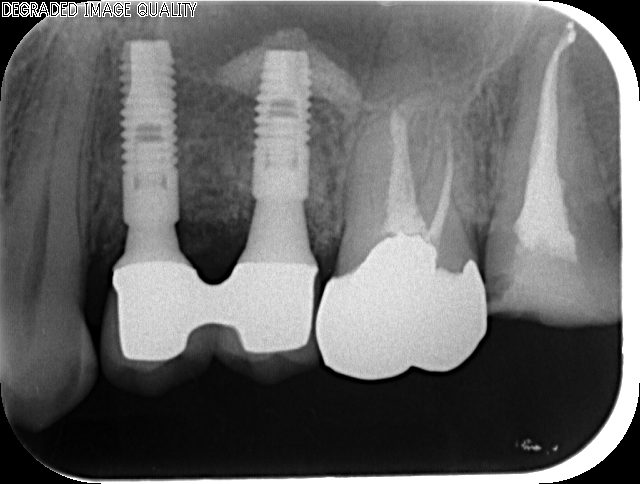

after

2010年 骨補填剤による上顎洞底の挙上とインプラント埋入

2018年

メインテナンス時